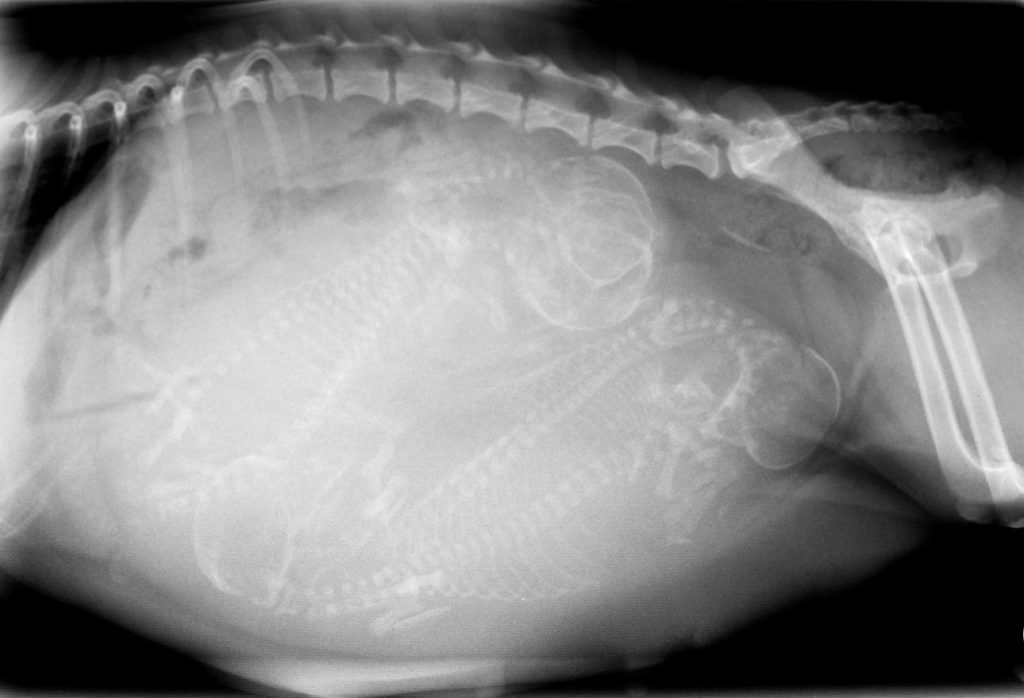

While an ultrasound seems like the obvious method, it will allow vets to check the viability of the puppies, but it is not a great method to accurately determine the number of puppies in the litter. Instead, an X-ray can help determine the number of puppies your Cane Corso is carrying in its litter.

To perform an X-ray, your dog has to be pregnant for a minimum of 45 days so that all the pups’ skeletons are visible.

pregnant dog X-ray

Image Credit: Trevor-Reeves, Shutterstock